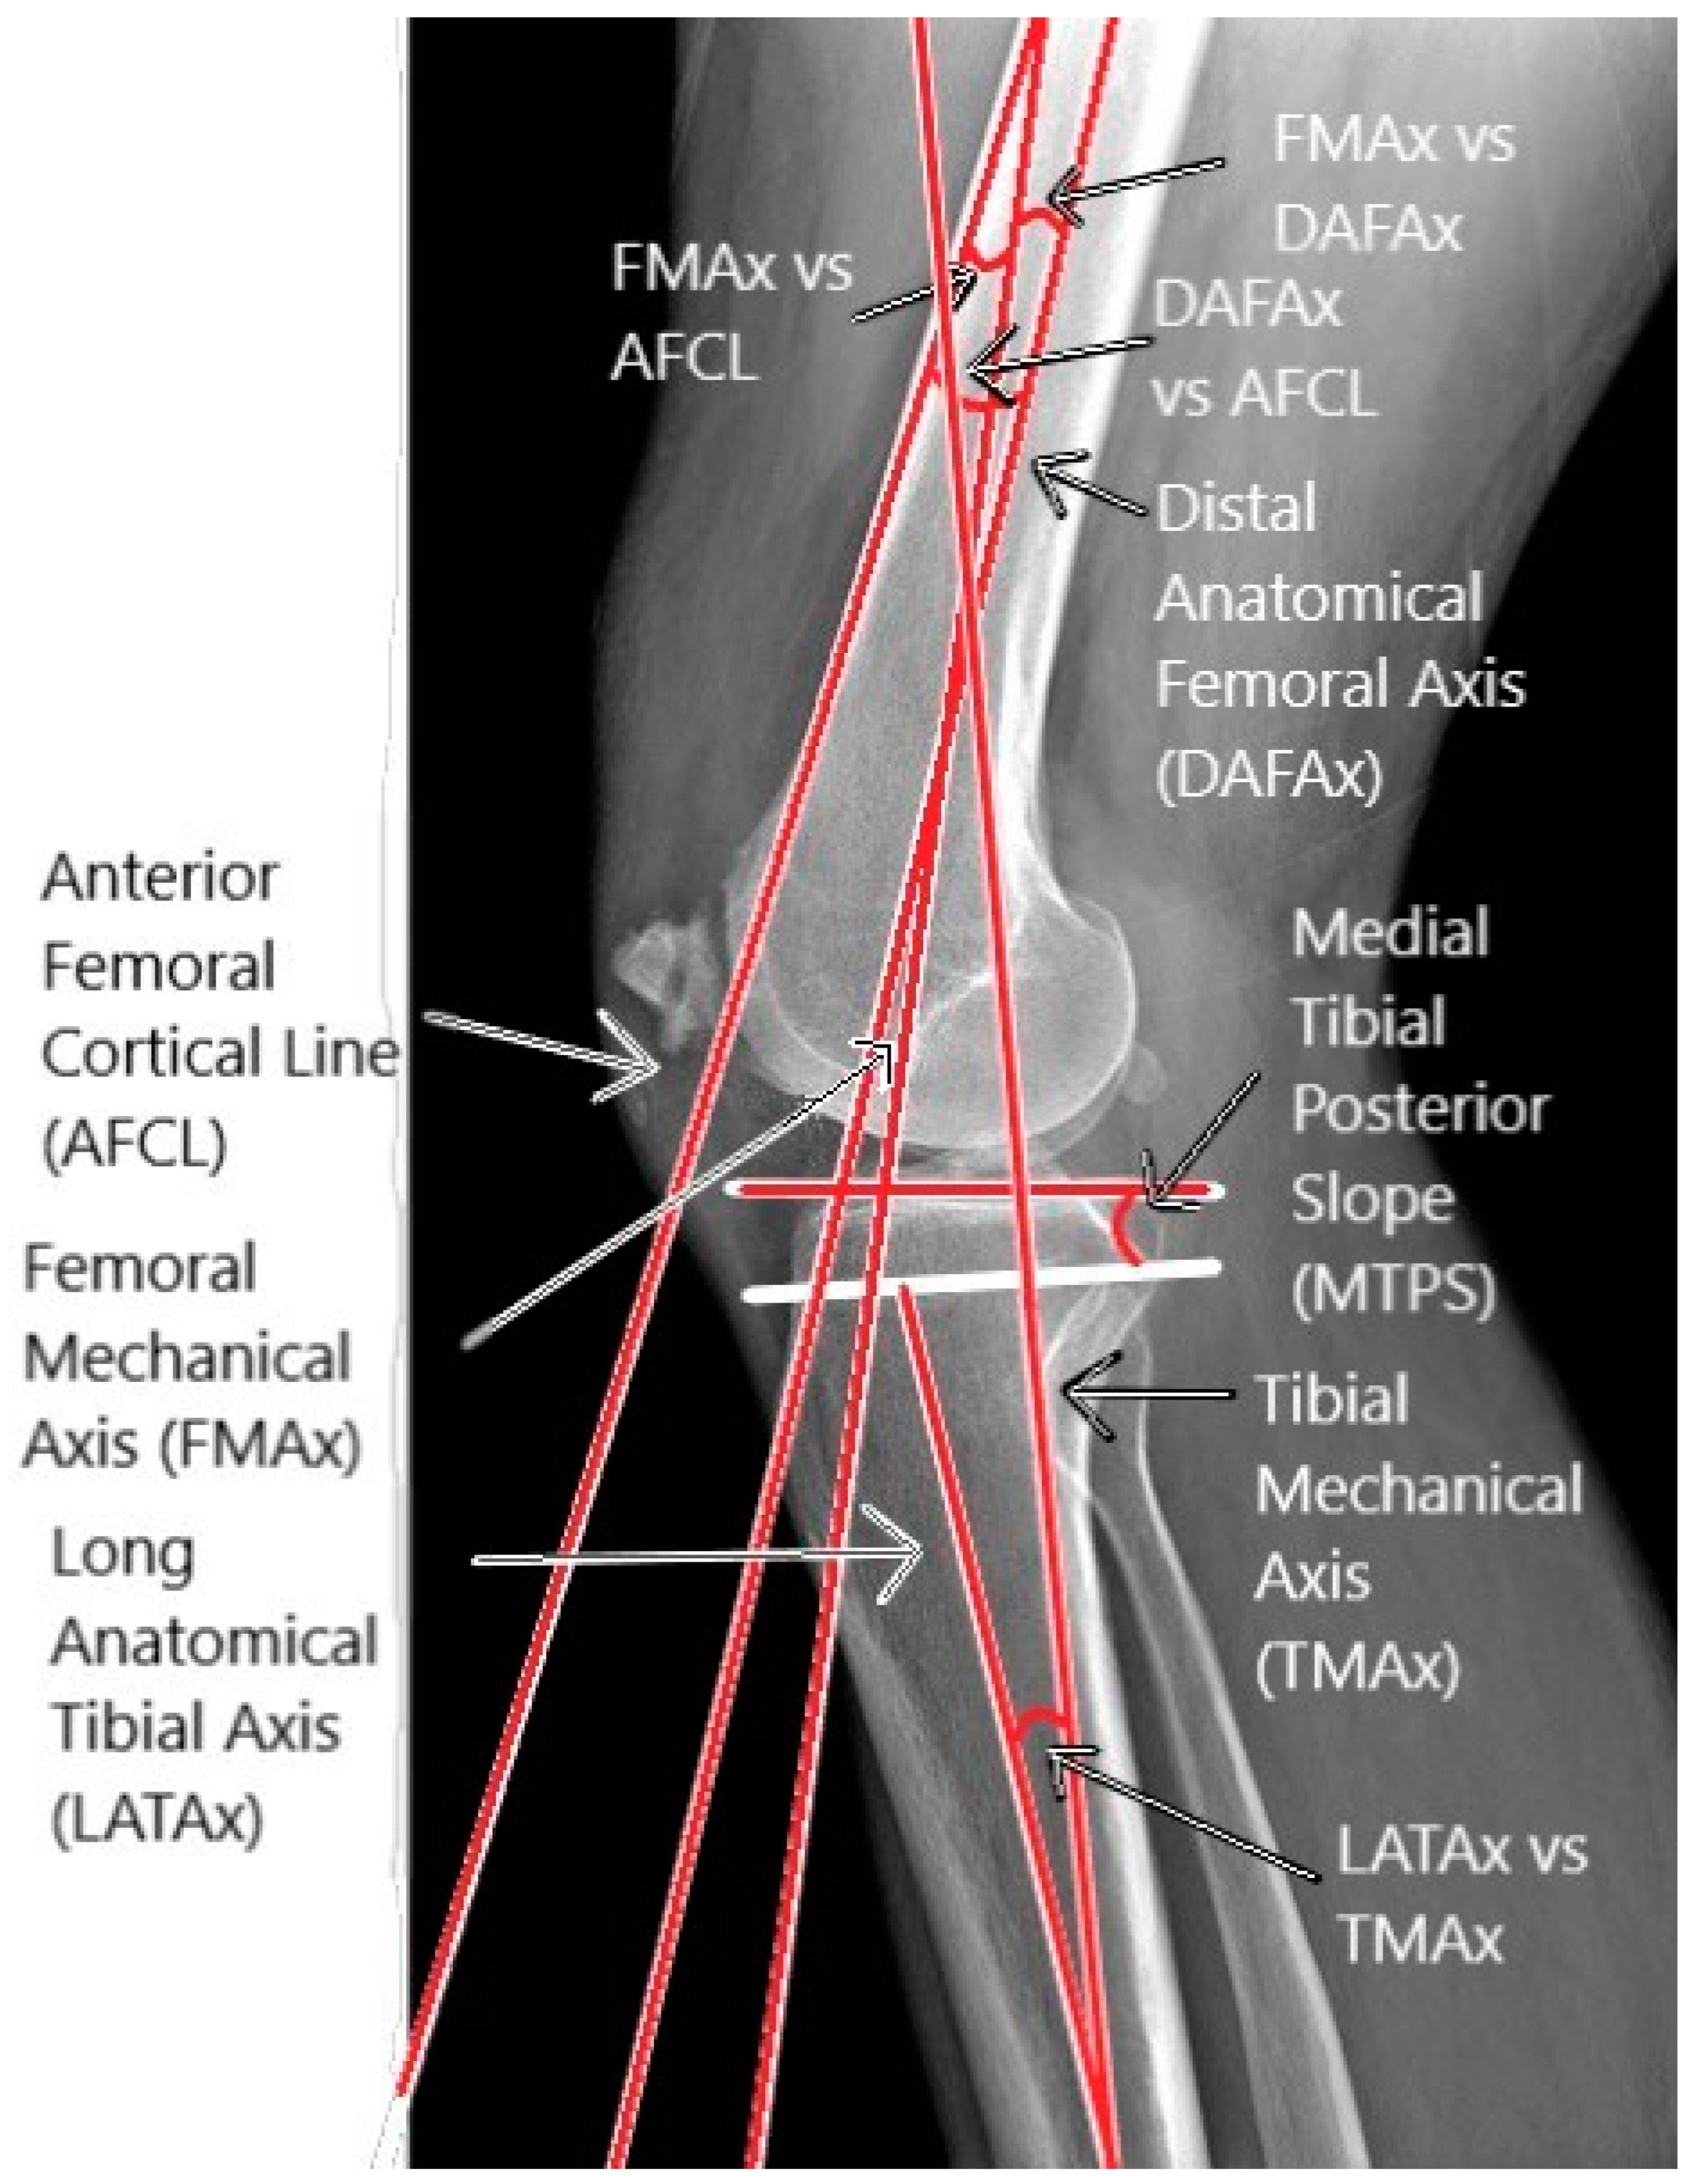

2.2. Sagittal Parameters

| FMAx vs. AFCL | −2 +/− 8.51 | −0.32 +/− 3.12 | 0.28 | 0.001 | −1.68 +/− 8.2 | −2.44 | 0.21 | 0.016 |

| FMAx vs. DAFAx (coronal) | 3.45 +/− 2.58 | 3.92 +/− 2.07 | 0.63 | 0.000 | −0.47 +/− 2.06 | −2.70 | 0.23 | 0.008 |

| AFCL vs. DAFAx | 5.45 +/− 8.76 | 4.24 +/− 3.2 | 0.32 | 0.000 | 1.22 +/− 8.33 | 1.73 | 0.15 | n.s. |

| FMAx vs. DAFAx (sagittal) | 4.29 +/− 1.47 | 4.73 +/− 1.57 | 0.59 | 0.000 | −0.44 +/− 1.38 | −3.78 | 0.32 | 0.000 |

| MTPS | 82.95 +/− 3.27 | 82.76 +/− 3.28 | 0.72 | 0.000 | 0.19 +/− 2.44 | 0.94 | 0.08 | n.s. |